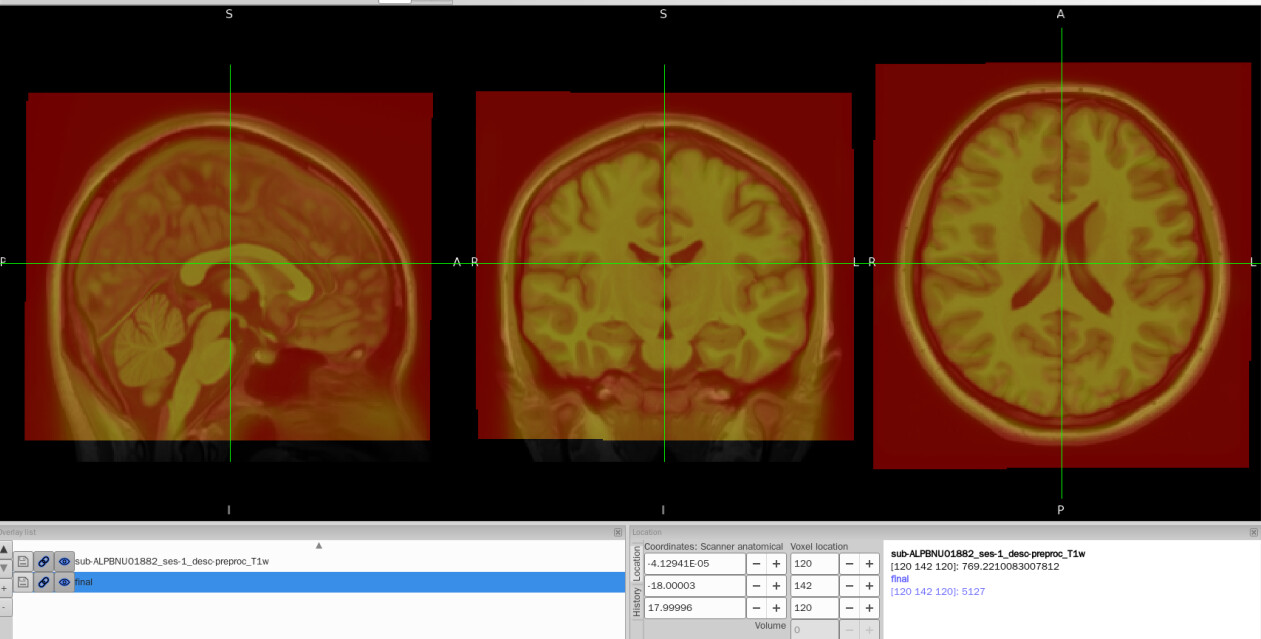

I tried to convert the ANTs-format warp (from-MNI152NLin2009cAsym_to-T1w_mode-image_xfm.h5) generated by fMRIPrep into FSL format (from-MNI152NLin2009cAsym_to-T1w_mode-image_xfm_fsl.nii.gz) using c3d affine tool, so that I could use it later in pyAFQ for tractography. The conversion itself works fine, but once I add intent code to FSL xfm header(intent code 2006), the warp seems to be damaged. To be specific, the FSL warp applied to MNI template shifted to the lower-left corner and it no longer aligns with the T1w image.